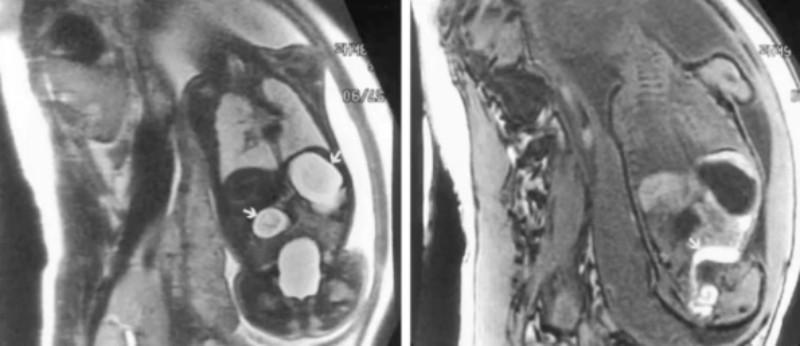

胎儿磁共振检查图像展示

——胎儿十二指肠闭锁,能清晰地显示对诊断特异的“双泡征”。